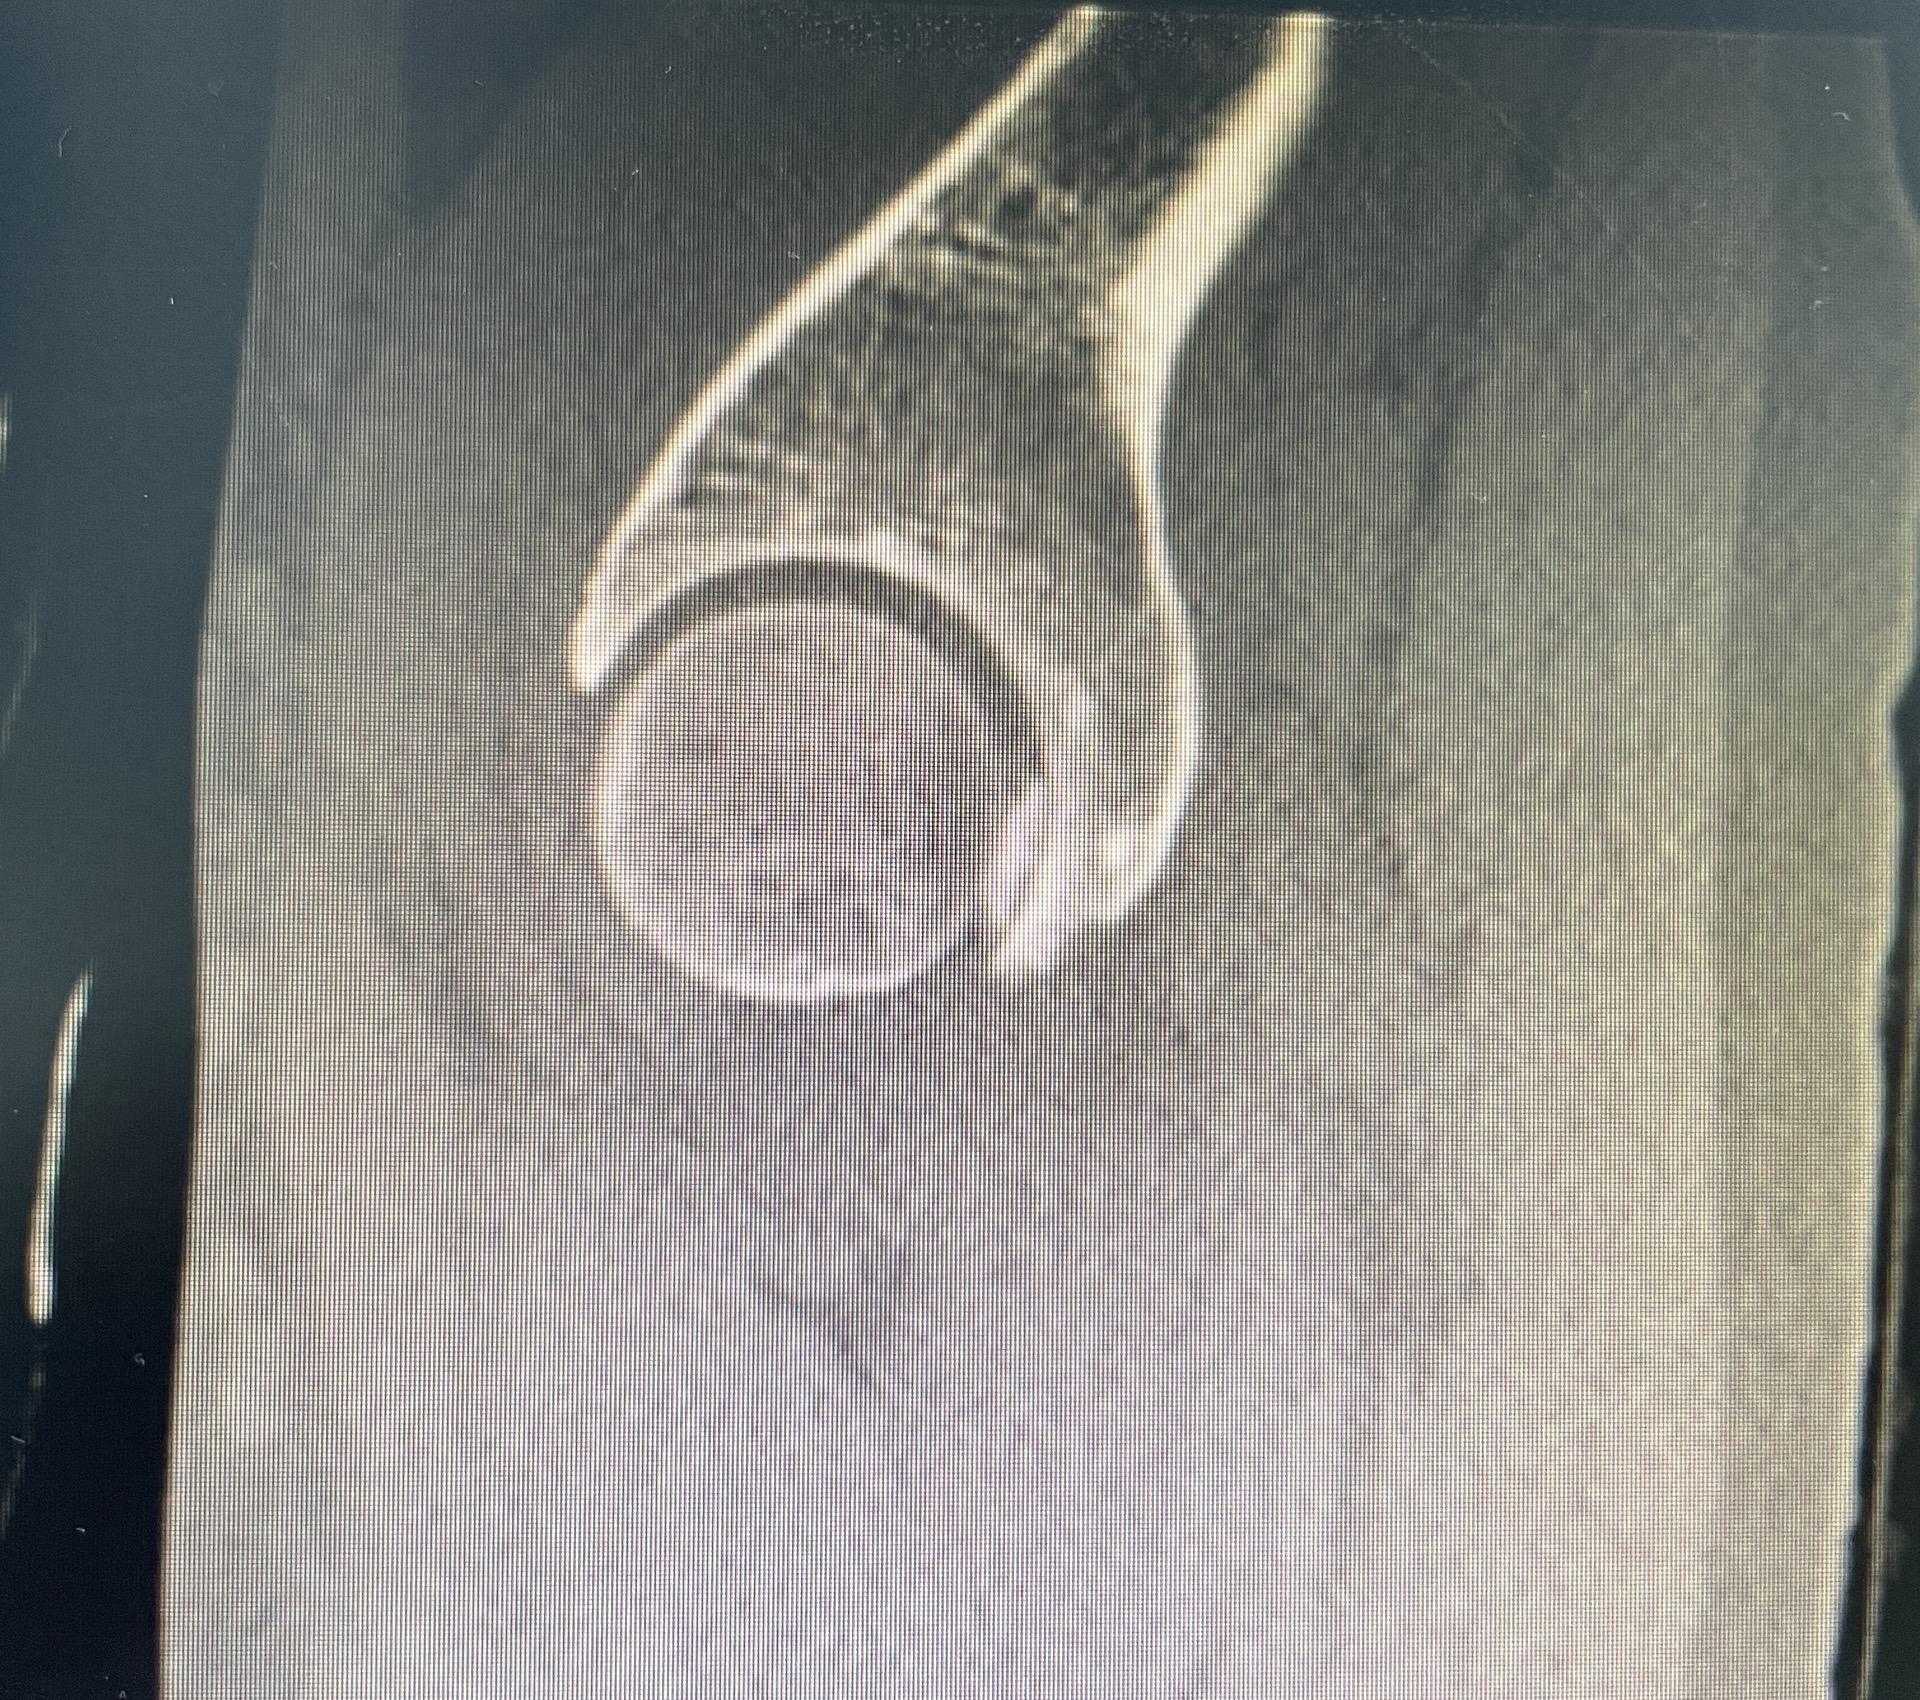

髋关节镜下游离体取出。髋关节脱位,股骨头圆韧带撕脱性骨折,髋关节镜下取出游离骨块。